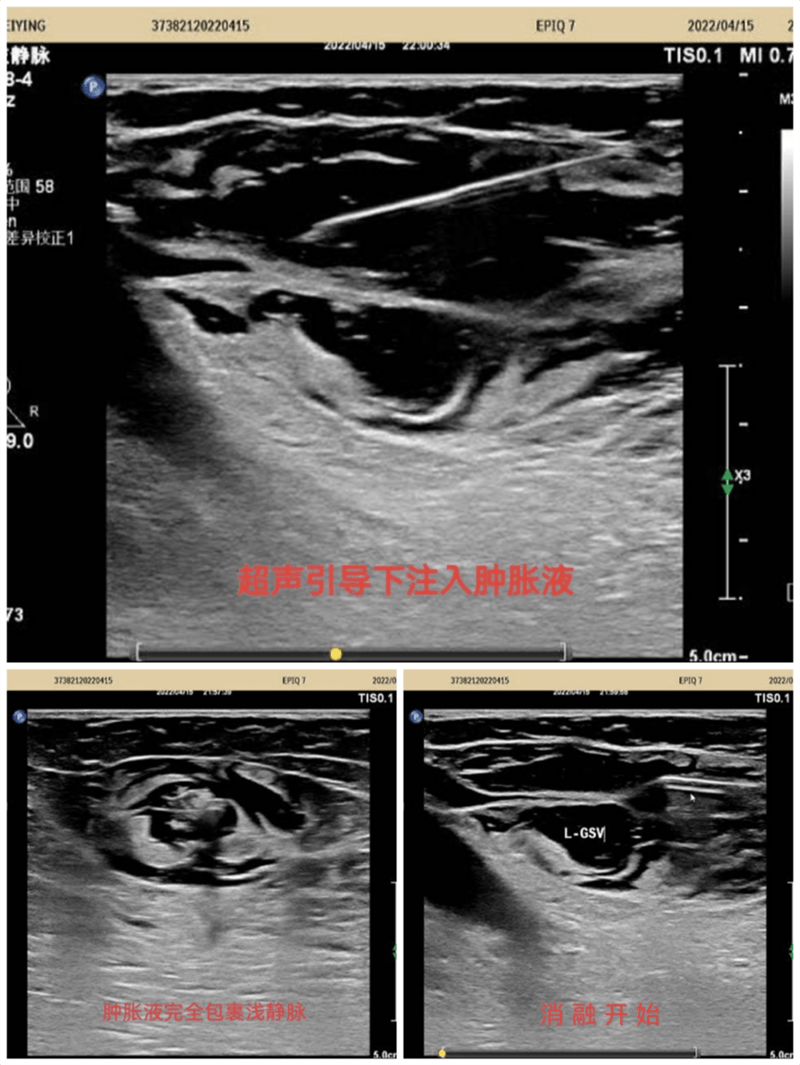

超聲引導(dǎo)下標(biāo)記大隱靜脈及曲張靜脈部位走行,體表投影部位標(biāo)記,在彩色多普勒超聲靜脈模式引導(dǎo)下實(shí)時(shí)監(jiān)測(cè),確定穿刺點(diǎn),局麻下穿刺進(jìn)針,確定穿刺成功后置入導(dǎo)絲,拔除穿刺針并沿導(dǎo)絲置入7F鞘管,拔出導(dǎo)絲,沿鞘管將消融電極置入要消融的大隱靜脈主干內(nèi),注入腫脹麻醉液,確認(rèn)大隱脈閉合,開啟移動(dòng)射頻消融導(dǎo)管,消融完畢后拔除鞘管及射頻導(dǎo)管再次超聲探查隱股靜脈交界處,確定無血栓形成。